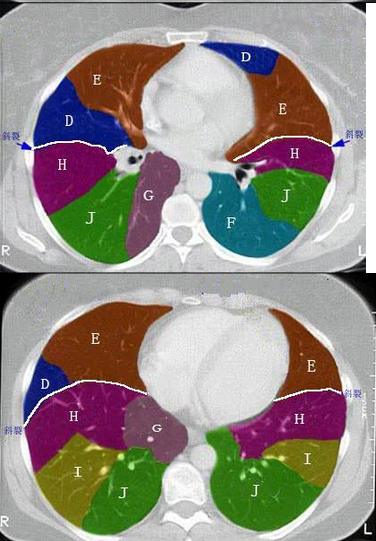

2、 结合肺段模式图,选出右肺中叶的组成()。

• A、B

• B、B+C

• C、B+C+D

• D、D+E

• E、D+E+F